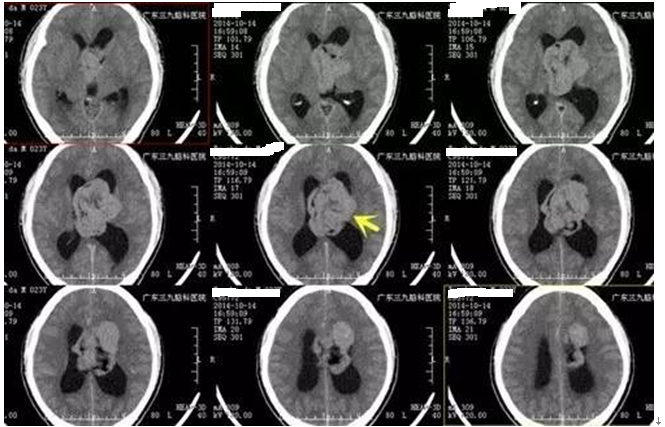

▲术前检查

中枢神经细胞瘤CT表现为边缘不规则的类圆形等或稍高密度肿块, 增强后呈不均匀轻到中等强化,常有钙化、囊性变及坏死。MR检查可见 瘤体呈蜂窝状或丝瓜瓤样囊变, 此为中枢神经细胞瘤的特征性表现。中枢神经细胞瘤多呈囊实性,实性部分T1WI、T2WI呈等或略高信号,囊性部分T1WI呈与脑脊液相等或略高的低信号,T2WI呈高信号。肿瘤边缘丝网状改变、 脑室内的信号不一及匍行性流空均是中枢神经细胞瘤特征性MR表现。本例患者CT平扫呈稍高密度分叶状,MR示异常T1WI高信号影,其内信号不均匀,边界清晰,范围约66.7mm×55.3mm×46.5mm,肿瘤体积较大,与侧脑室壁、丘脑、下丘脑及大脑脑静脉等中线结构紧邻。